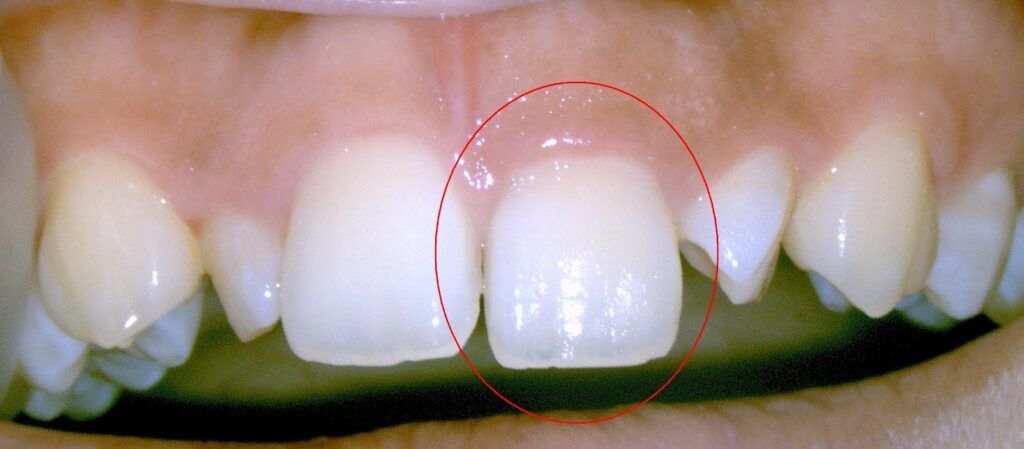

Dr.:歯の神経(歯髄)は、強打の為断絶してしまい、助かりません。かといって抜歯はしません。壊死してしまった根管内の歯髄を綺麗にする根管治療をします。

赤丸が膿んでいる病変部